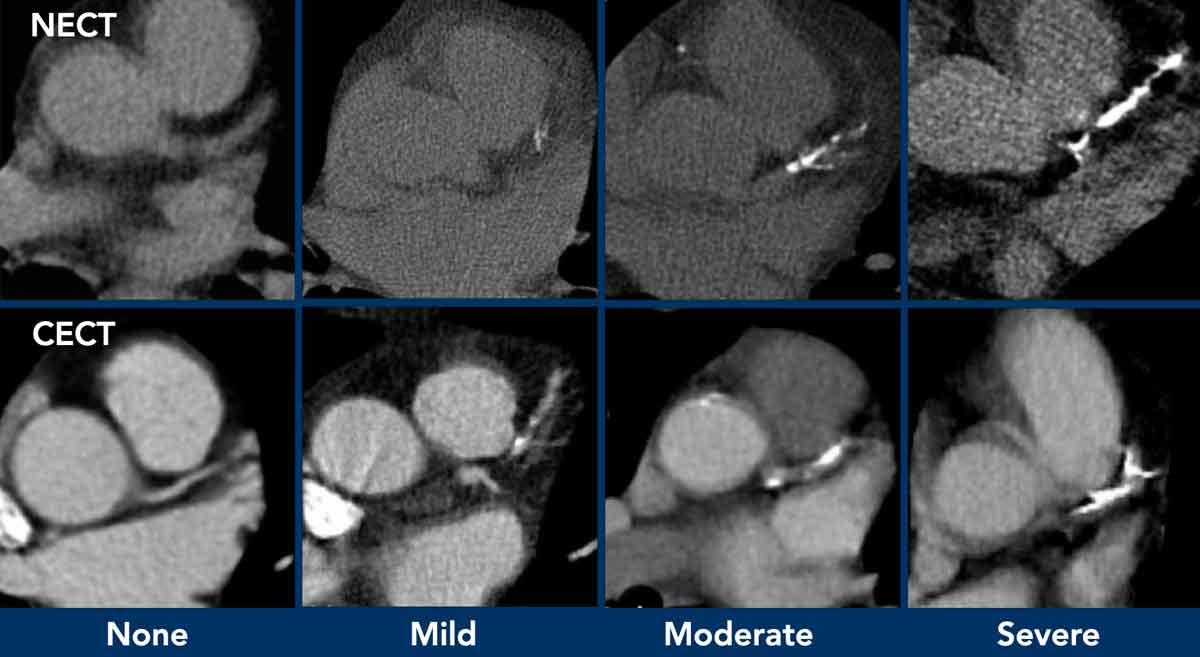

Khuyến cáo đánh giá định lượng bằng mắt mức độ vôi hóa van động mạch chủ thành nhẹ, trung bình và nặng (hình).

Có thể đưa khuyến nghị vào báo cáo chẩn đoán hình ảnh (xem Hình).

Đề xuất là thực hiện đánh giá vôi hóa bằng mắt thường theo thang điểm đơn giản: Không có, Nhẹ, Trung bình hoặc Nặng, dựa trên tổng hợp các phát hiện ở cả ba động mạch vành (xem Hình).

Có thể bổ sung khuyến nghị vào báo cáo chẩn đoán hình ảnh (hình)